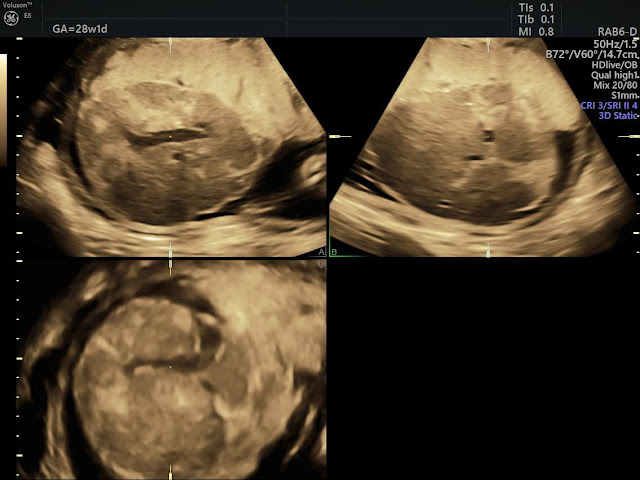

U máu bánh nhau (Chorangioma)

U máu bánh nhau (chorangioma) là khối u mạch máu lành tính của bánh nhau – cơ quan tạm thời trong thai kỳ có chức năng cung cấp dưỡng chất và oxy cho thai nhi. Chorangioma gặp ở khoảng 0,5% đến 1% các thai kỳ. Phần lớn các khối u này có kích thước nhỏ, không gây triệu chứng và không ảnh hưởng đến tiến triển của thai kỳ. Tuy nhiên, những khối u lớn hơn (>4–5 cm) có thể dẫn đến biến chứng. Tỷ lệ chorangioma lớn ước tính dao động từ 1/3.500 đến 1/9.000 ca sinh (tương đương 0,29%–0,11%).

Bạn sẽ được chỉ định siêu âm định kỳ có Doppler để theo dõi:

Kích thước khối u

Tăng trưởng thai

Lượng nước ối

Dấu hiệu thiếu máu hoặc suy tim thai